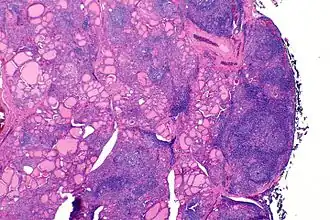

Macroscopiquement, le goitre est symétrique, non adhérent aux éléments péri-thyroïdiens et présente une surface capsulaire discrètement bosselée[1].

En microscopie les lésions consistent en une association de fibrose interstitielle, d'infiltration lymphoïde et de destruction épithéliale[1],[2]. Le degré de fibrose est très variable[1]. L'infiltration lymphoïde présente une organisation en follicules avec des lymphocytes B au centre et des lymphocytes T dans le cortex[2]. Les cellules épithéliales thyroïdiennes sont également modifiées, apparaissant élargies et acidophiles (cellules de Hürthle)[2].